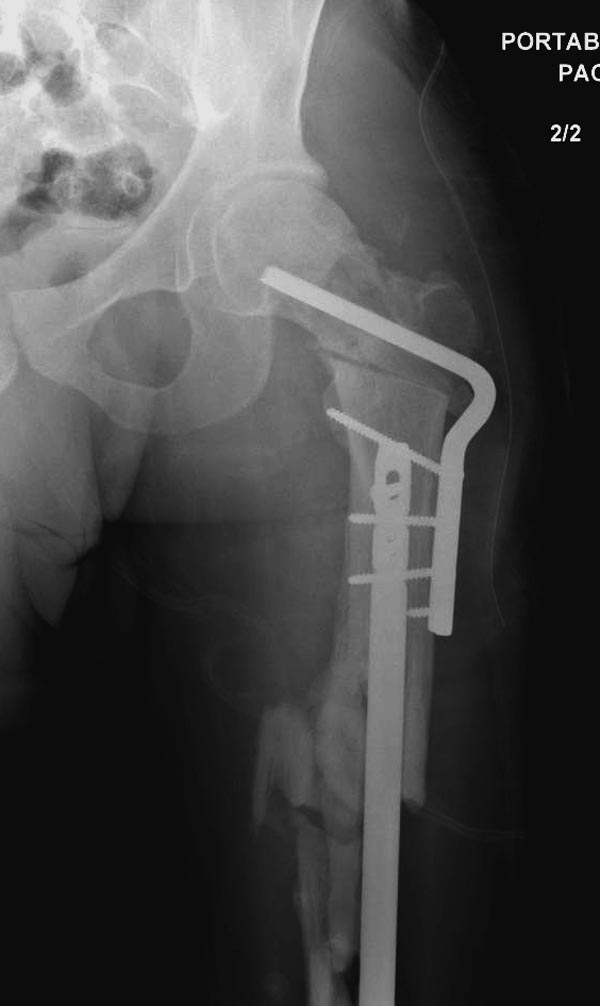

Здесь выставлен ренгенограммы больного, ему 21, травму получил в

результате высокоскоростной погони на украденной машине, которая

закончилась смертью трех остальных“боевых комрадов”. Начатую коллегой

открытую операцию на шейке пришлось закончить мне, установкой винтов и

ретроградной фиксацией бедра. Выписка в обычное сроки и наблюдался

амбулаторно. Каждый раз напоминали о возможности осложнений ввиде

несращения! По истечению 4 месяцев появились признаки варусной

деформации. На СТ срезах несращение шейки и бедра. Риминг, замена на

более толстый гвоздь и вальгусная остеотомия.